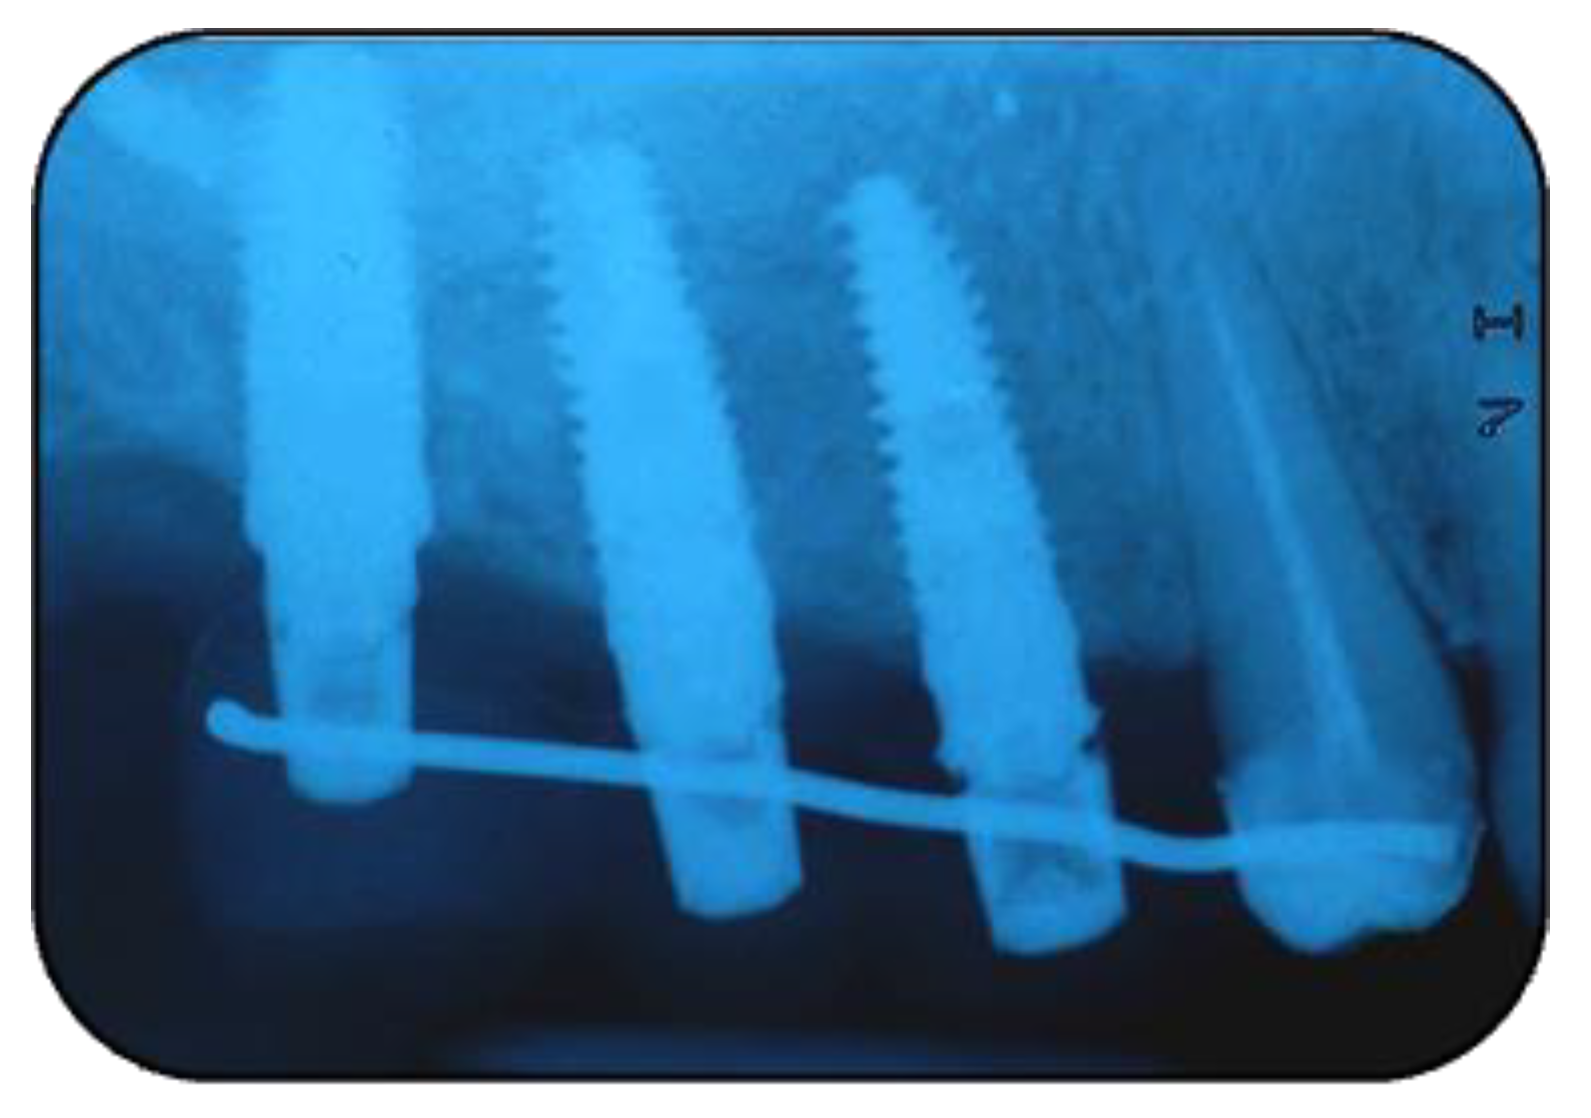

2.1. Surgical Procedures